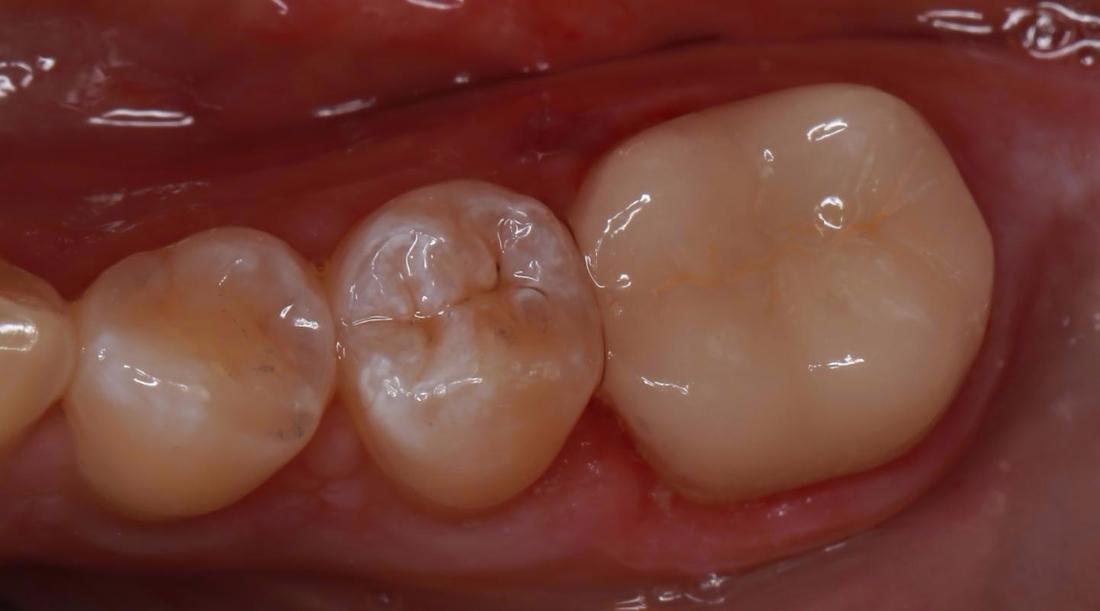

This patient came in with a large filling on the back molar that was becoming decayed. To save the remaining structure of the tooth Dr Kiaee used a dental crown to cover the existing tooth and restore the integrity.

A crown can be used to cover a weak or damaged tooth. Besides strengthening a damaged tooth, a crown can improve the tooth's appearance, shape and colour.